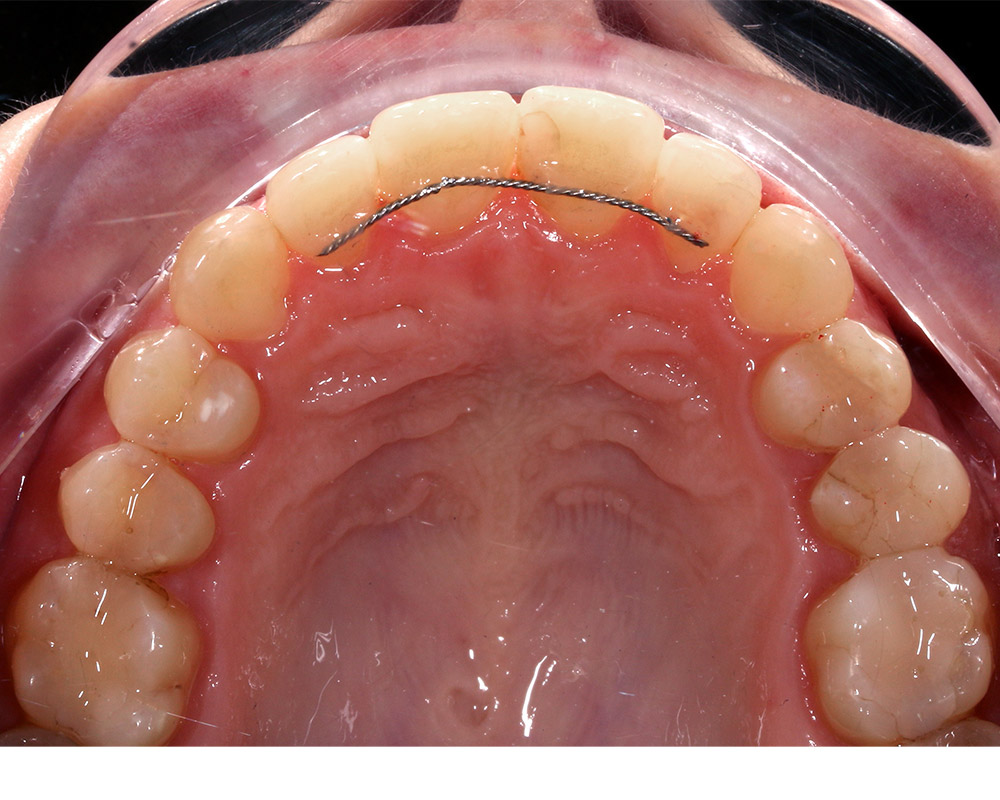

Кейс 13

Булгач (Мочалова) Галина Игоревна

Количество кап ВЧ 19

Количество кап НЧ 24

ДО

ПОСЛЕ